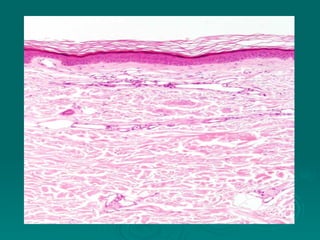

Connective tissues support and bind together other structures throughout the body. They are composed of connective tissue cells, ground substance, and fibers. Connective tissues have few cells separated by an abundant intercellular substance containing fibers. Their main functions are to bind tissues, provide mechanical support, store fat and minerals, allow for metabolite exchange, and aid in repair and healing. Connective tissues are classified as connective tissue proper, which includes loose and dense connective tissues, and specialized connective tissues like cartilage, bone, and blood.